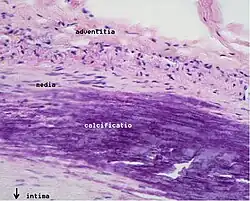

Calcification and lipids

Calcification forms among vascular smooth muscle cells of the surrounding muscular layer, specifically in the muscle cells adjacent to atheromas and on the surface of atheroma plaques and tissue.[70] In time, as cells die, this leads to extracellular calcium deposits between the muscular wall and outer portion of the atheromatous plaques. With the atheromatous plaque interfering with the regulation of calcium deposition, it accumulates and crystallizes. A similar form of intramural calcification, presenting the picture of an early phase of arteriosclerosis, appears to be induced by many drugs that have an antiproliferative mechanism of action (Rainer Liedtke 2008).

- The fibro-lipid (fibro-fatty) plaque is characterized by an accumulation of lipid-laden cells underneath the intima of the arteries, typically without narrowing the lumen due to compensatory expansion of the bounding muscular layer of the artery wall. Beneath the endothelium, there is a "fibrous cap" covering the atheromatous "core" of the plaque. The core consists of lipid-laden cells (macrophages and smooth muscle cells) with elevated tissue cholesterol and cholesterol ester content, fibrin, proteoglycans, collagen, elastin, and cellular debris. In advanced plaques, the central core of the plaque usually contains extracellular cholesterol deposits (released from dead cells), which form areas of cholesterol crystals with empty, needle-like clefts. At the periphery of the plaque are younger "foamy" cells and capillaries. These plaques usually produce the most damage to the individual when they rupture. Cholesterol crystals may also play a role.[73]

- The fibrous plaque is also localized under the intima, within the arterial wall, resulting in thickening and expansion of the wall and, sometimes, spotty localized narrowing of the lumen with some atrophy of the muscular layer. The fibrous plaque contains collagen fibers (eosinophilic), precipitates of calcium (hematoxylinophilic), and, rarely, lipid-laden cells.

However, atheromas within the vessel wall are soft and fragile with little elasticity. Arteries constantly expand and contract with each heartbeat, i.e., the pulse. In addition, the calcification deposits between the outer portion of the atheroma and the muscular wall, as they progress, lead to a loss of elasticity and stiffening of the artery as a whole.

The calcification deposits,[74] after they have become sufficiently advanced, are partially visible on coronary artery computed tomography or electron beam tomography (EBT) as rings of increased radiographic density, forming halos around the outer edges of the atheromatous plaques, within the artery wall. On CT, >130 units on the Hounsfield scale (some argue for 90 units) has been the radiographic density usually accepted as clearly representing tissue calcification within arteries. These deposits demonstrate unequivocal evidence of the disease, relatively advanced, even though the lumen of the artery is often still normal by angiography.